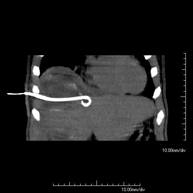

- PAAF (Punción) Abdominal guiada por TC Consiste en obtener una muestra de tejido de una determinada lesión localizada en la cavidad abdominal. Para ello se administra anestesia local sobre la zona de la punción, la cual se realiza con agujas de fino calibre. Todo el procedimiento se realiza controlado con imágenes obtenidas por Tomografía Computarizada (TC) en varios momentos de la punción, mediante el uso de un equipo de Fluroscopia-TC. Tras la prueba, el paciente permanece unas horas hospitalizado para controlar su evolución. Es necesario aportar pruebas de coagulación antes de la punción. Consiste en obtener una muestra de tejido de una determinada lesión localizada en la cavidad abdominal. Para ello se administra anestesia local sobre la zona de la punción, la cual se realiza con agujas de fino calibre. Todo el procedimiento se realiza controlado con imágenes obtenidas por Tomografía Computarizada (TC) en varios momentos de la punción, mediante el uso de un equipo de Fluroscopia-TC. Tras la prueba, el paciente permanece unas horas hospitalizado para controlar su evolución. Es necesario aportar pruebas de coagulación antes de la punción.

- Biopsia abdominal guiada por TC Consiste en obtener una muestra de tejido de una determinada lesión localizada en la cavidad abdominal. En ocasiones se realiza bajo sedación, con la ayuda del equipo de anestesia. Se utilizan agujas que permiten la obtención de un cilindro de la lesión a estudiar, que se enviará a Anatomía Patológica para su análisis histológico. Todo el procedimiento se realiza controlado con imágenes obtenidas por Tomografía Computarizada (TC) en varios momentos de la biopsia, mediante el empleo de Fluoroscopia-TC. Tras la prueba, el paciente permanece hospitalizado para controlar su evolución. Es necesario aportar pruebas de coagulación antes de la punción. Consiste en obtener una muestra de tejido de una determinada lesión localizada en la cavidad abdominal. En ocasiones se realiza bajo sedación, con la ayuda del equipo de anestesia. Se utilizan agujas que permiten la obtención de un cilindro de la lesión a estudiar, que se enviará a Anatomía Patológica para su análisis histológico. Todo el procedimiento se realiza controlado con imágenes obtenidas por Tomografía Computarizada (TC) en varios momentos de la biopsia, mediante el empleo de Fluoroscopia-TC. Tras la prueba, el paciente permanece hospitalizado para controlar su evolución. Es necesario aportar pruebas de coagulación antes de la punción.

- Drenaje abdominal guiado por TC (abscesos, colecciones) Consiste en colocar un catéter de drenaje sobre una colección líquida localizada en la cavidad abdominal, con la intención de vaciar el máximo posible dicha colección. El paciente deberá mantener el drenaje algunos días, normalmente hasta que no sea productivo. A menudo se realiza bajo sedación, con la ayuda del equipo de anestesia. Todo el procedimiento se realiza controlado con imágenes obtenidas por Tomografía Computarizada (TC) en varios momentos de la prueba mediante el empleo de Fluoroscopia-TC. Tras la prueba, el paciente permanece hospitalizado. Es necesario aportar pruebas de coagulación antes de la prueba. Consiste en colocar un catéter de drenaje sobre una colección líquida localizada en la cavidad abdominal, con la intención de vaciar el máximo posible dicha colección. El paciente deberá mantener el drenaje algunos días, normalmente hasta que no sea productivo. A menudo se realiza bajo sedación, con la ayuda del equipo de anestesia. Todo el procedimiento se realiza controlado con imágenes obtenidas por Tomografía Computarizada (TC) en varios momentos de la prueba mediante el empleo de Fluoroscopia-TC. Tras la prueba, el paciente permanece hospitalizado. Es necesario aportar pruebas de coagulación antes de la prueba.